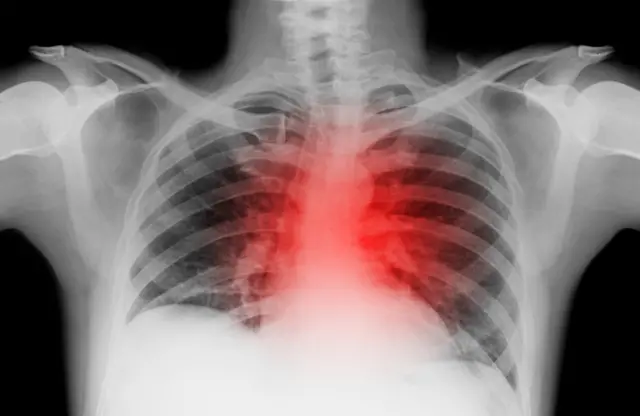

‘હજારો ઑપરેશન’ કરનારા જામનગરના યુવાન કાર્ડિયોલૉજિસ્ટનું ‘હૃદયરોગના હુમલામાં’ નિધન કેવી રીતે થયું?

મંગળવારે વહેલી સવારે જામનગરના ‘જાણીતા’ કાર્ડિયોલૉજિસ્ટ ગૌરવ ગાંધીનું 41 વર્ષની યુવાન વયે ‘હૃદયરોગના હુમલા’માં નિધન થયું હતું.

હૃદયના ‘હજારો ઑપરેશન’ કરનારા કાર્ડિયોલૉજિસ્ટના અકાળ મૃત્યુની ઘટનાએ યુવાન વયે હૃદયરોગના હુમલામાં થતાં મૃત્યુને લઈને ‘ચિંતા જન્માવી છે.’

ગુજરાત સહિત ઘણાં અન્ય સ્થળોએ નાચતાં-ગાતાં, રમતાં, ચાલતાં ચાલતાં પણ કેટલાક યુવાનોને હૃદયરોગના હુમલામાં જીવ ગુમાવ્યો હોય એવી ઘટનાઓ તાજેતરમાં સામે આવી છે.

આ કેસમાં આવા જ એક ‘નિષ્ણાત’ આ સમસ્યાનો ‘ભોગ બની જતાં’ યુવાનોમાં પોતાના હૃદયને લગતી સમસ્યાઓ અંગે ‘ચિંતા જન્મે’ એ સ્વાભાવિક છે.